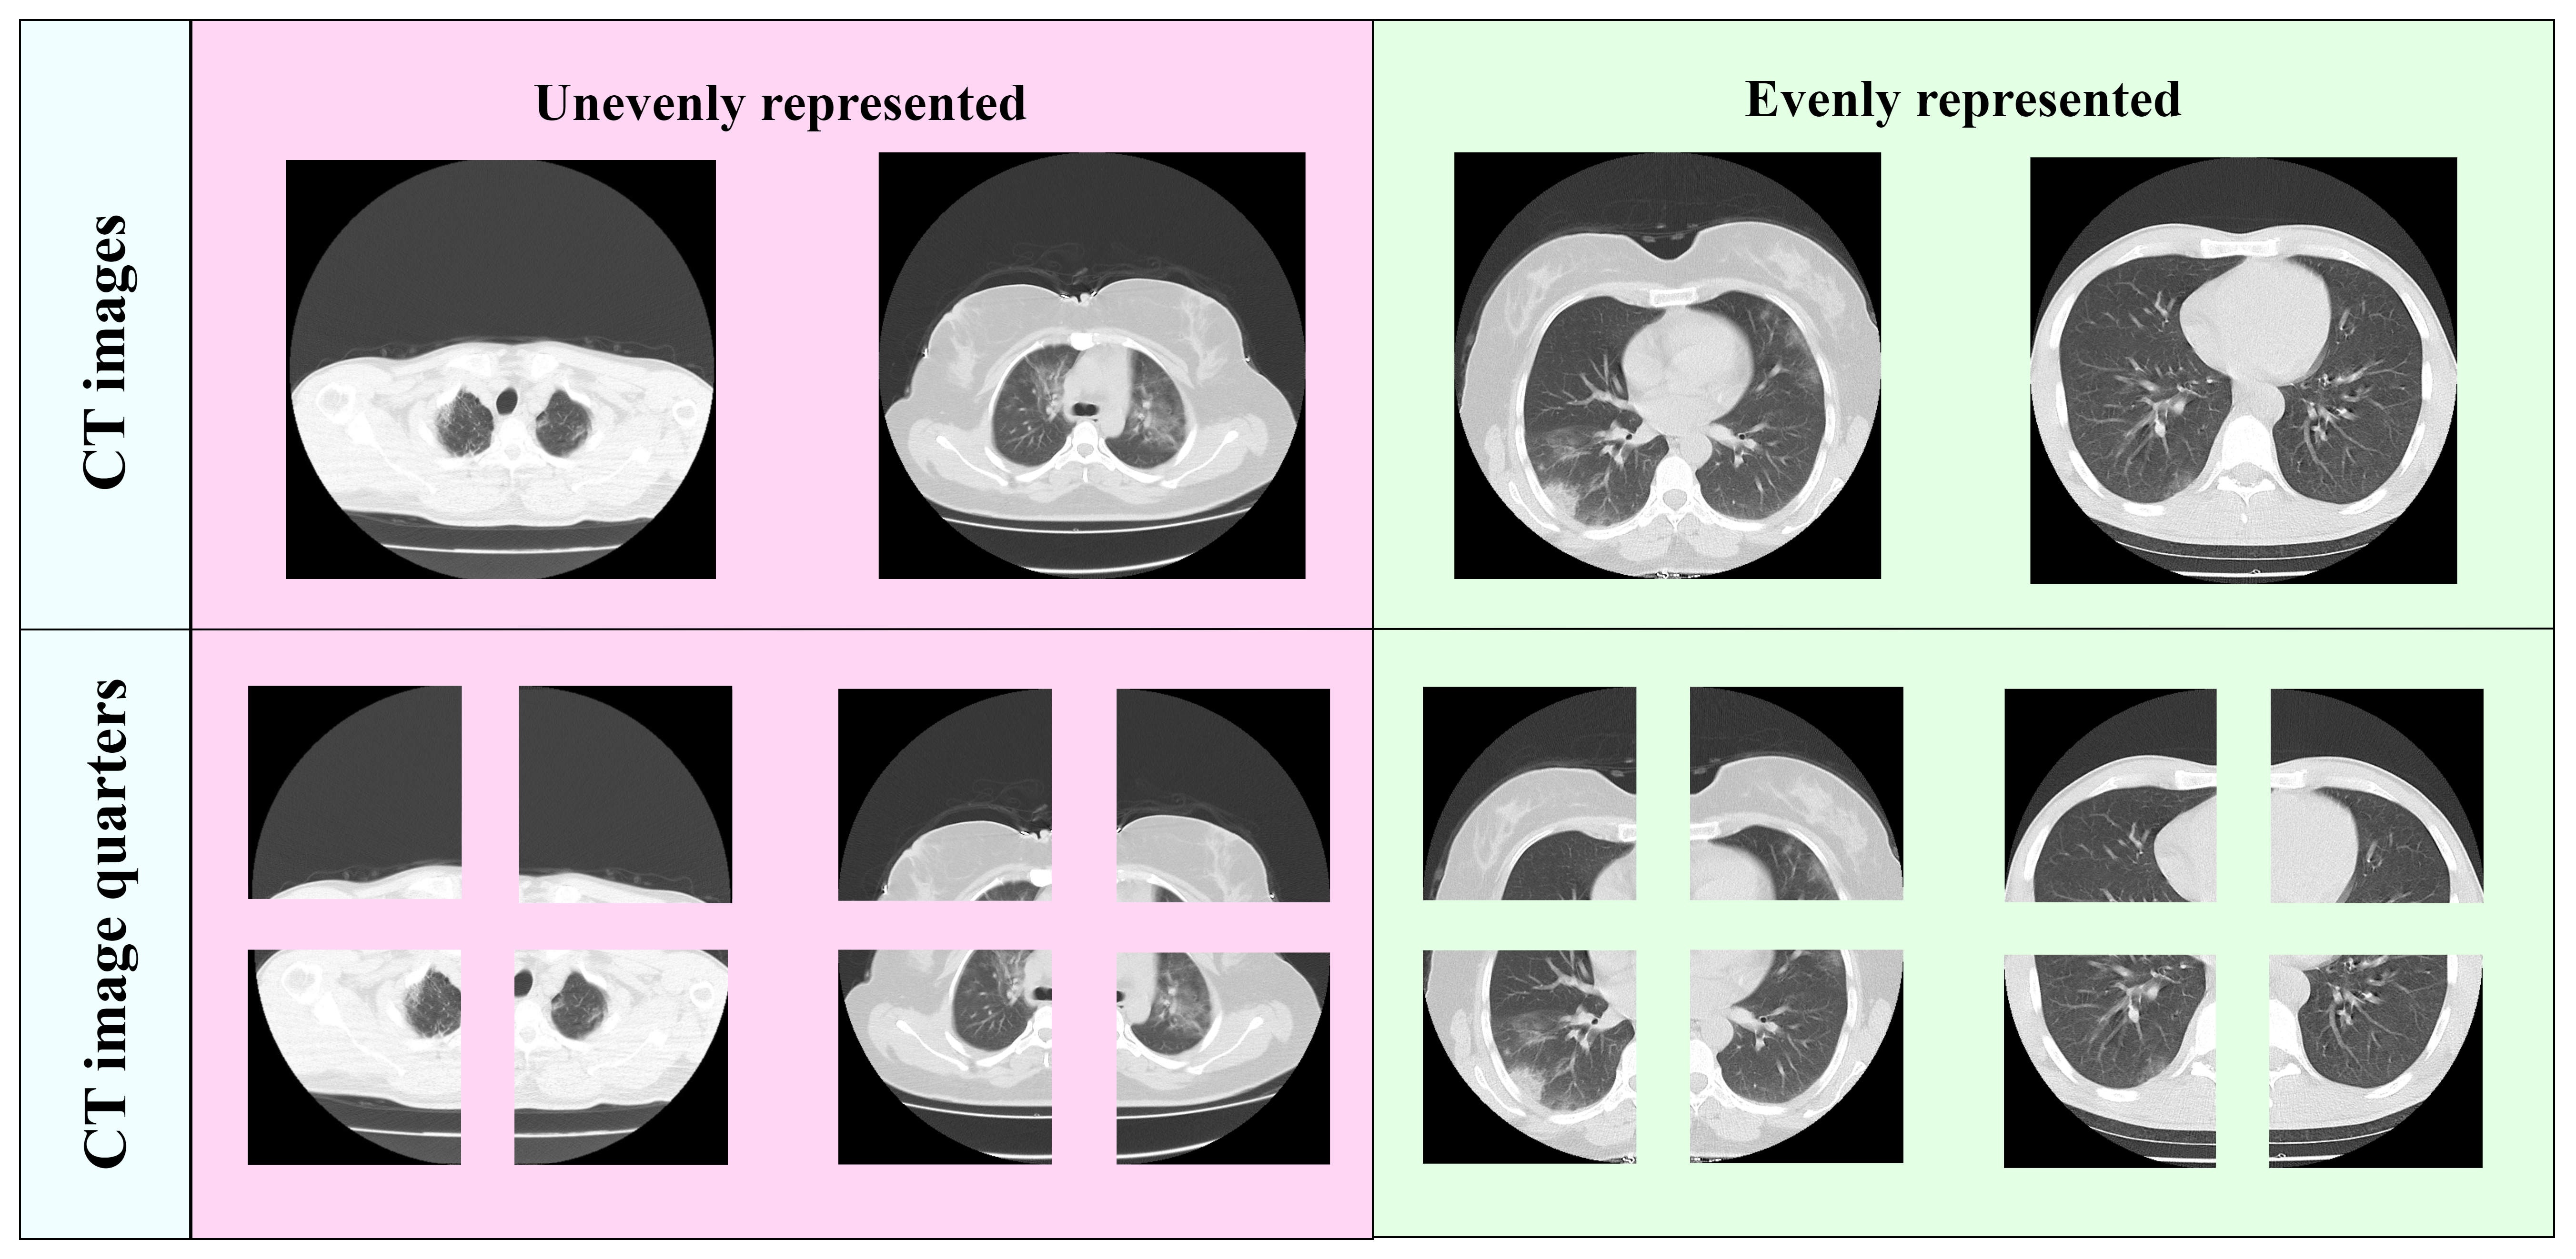

To compare performance more effectively in terms of generalization ability, it’s important to highlight that the validation labels are naturally noisy. This is because they are based on radiologists’ direct estimation of the infection percentage by visually comparing the infected areas to the total lung volume. However, despite the difficulty of learning from such noisy data, our approach shows a strong capacity to generalize in domain adaptation scenarios. Moreover, concerning our method for dividing CT images into regions of interest, we recognize that in many CT slices, the division into four lung quarters is not always uniform and may not consistently represent the complete anatomical structure as shown in Figure 6.

Despite these potential limitations in precisely dividing the lungs into uniform quarters, our model still performs competitively compared to the leading approaches. For future work, we aim to enhance this splitting process by employing more advanced techniques, such as dedicated lung detection or segmentation methods, to achieve greater consistency and accuracy in dividing the lungs into quarters. By incorporating these refined approaches, we expect to improve the anatomical relevance of the segmentation, leading to even better model performance in capturing the complex patterns present in the lung images.